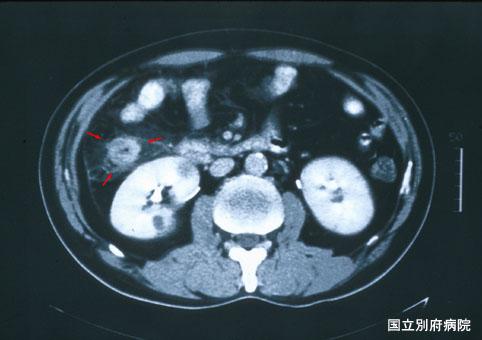

대장암과의 감별이 어려웠던 호산구증다증에 동반하는 허혈성 대방염(증례제시:국립 벳부병원)

염증성 및 궤양성질환/허혈성 장염(혈전증 포함)

부위(장기별)

대장/상행

검사방법

CT

종양의 최대경(밀리미터)

40이상